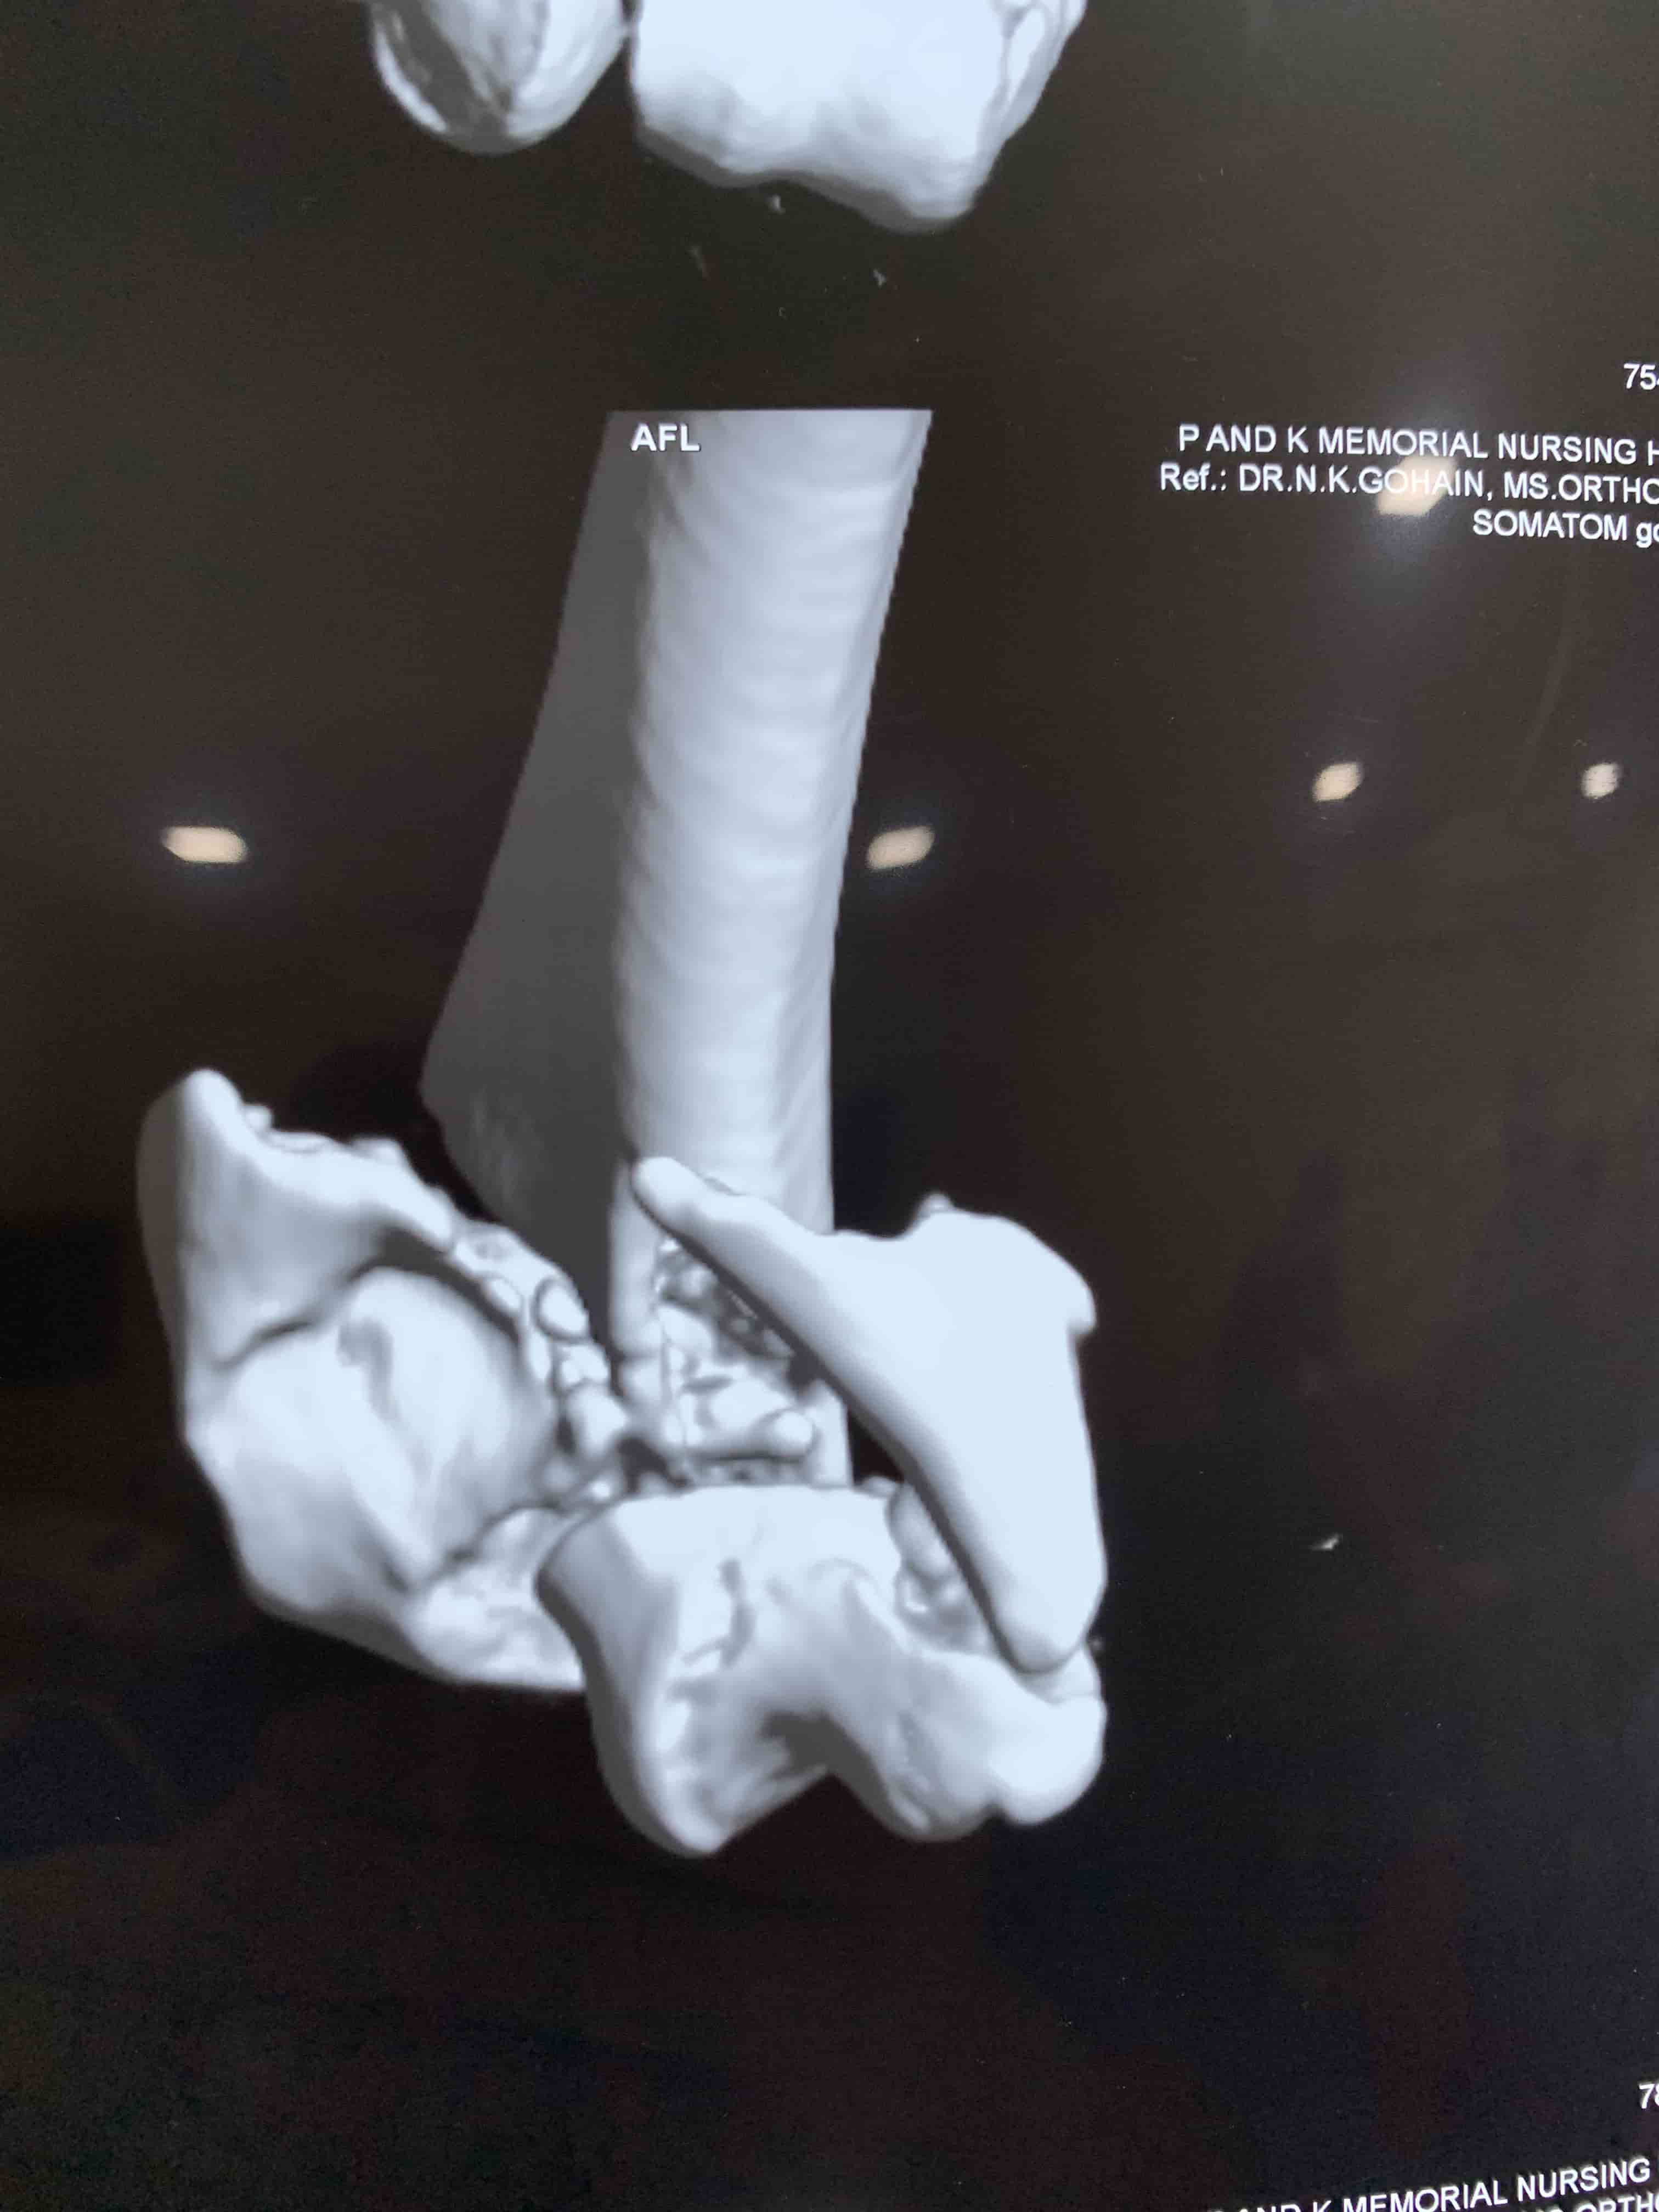

Complex Distal Humerus Comminuted Fracture

Complex Distal Humerus Comminuted Fracture

Complex Distal Humerus Comminuted Fracture

Complex Distal Humerus Comminuted Fracture

Complex Distal Humerus Comminuted Fracture

Complex Distal Humerus Comminuted Fracture

Complex Distal Humerus Comminuted Fracture

Complex Distal Humerus Comminuted Fracture

Complex Distal Humerus Comminuted Fracture

Complex Distal Humerus Comminuted Fracture

Complex Distal Humerus Comminuted Fracture

Complex Distal Humerus Comminuted Fracture

Complex Distal Humerus Comminuted Fracture

Complex Distal Humerus Comminuted Fracture